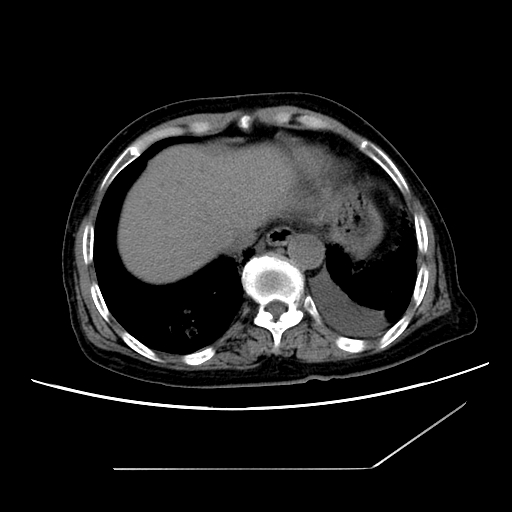

标题: CT25393:病人45岁,咳嗽,吐黄痰带血丝,发热,胸闷月余 [打印本页]

标题: CT25393:病人45岁,咳嗽,吐黄痰带血丝,发热,胸闷月余

1、左肺中央型肺癌并双肺弥漫性转移   2、双肺部感染    3、肺大泡     4、左侧胸腔积液

双侧肺弥漫性病变,可见“空泡征”及“蜂窝征”,考虑肺泡癌可能性大,左侧胸腔积液,考虑胸膜受累可能!

考虑肺泡癌,建议排除感染。

考虑肺泡癌

1)不排除肺泡癌可能。2)左侧胸腔积液。